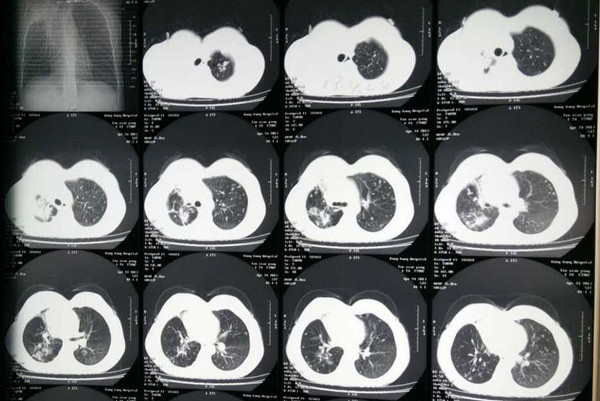

要获得肺结核的正确诊断,必须结合病史、体格检查、结核菌素(PPD)试验、实验室检查、X线检查等各项资料,其中以痰结核菌检查最为重要,(因痰涂片检查阳性的肺结核病人是能够排出结核病菌的,故传染性最大,也是结核病的主要传染源)加以综合分析,最终确诊是不是患上了肺结核和有没有传染性。